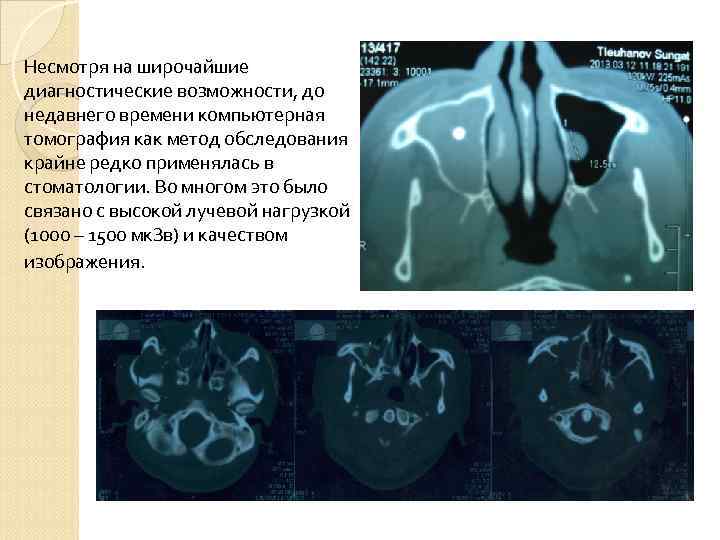

Несмотря на широчайшие диагностические возможности, до недавнего времени компьютерная томография как метод обследования крайне редко применялась в стоматологии. Во многом это было связано с высокой лучевой нагрузкой (1000 – 1500 мк. Зв) и качеством изображения.

Несмотря на широчайшие диагностические возможности, до недавнего времени компьютерная томография как метод обследования крайне редко применялась в стоматологии. Во многом это было связано с высокой лучевой нагрузкой (1000 – 1500 мк. Зв) и качеством изображения.